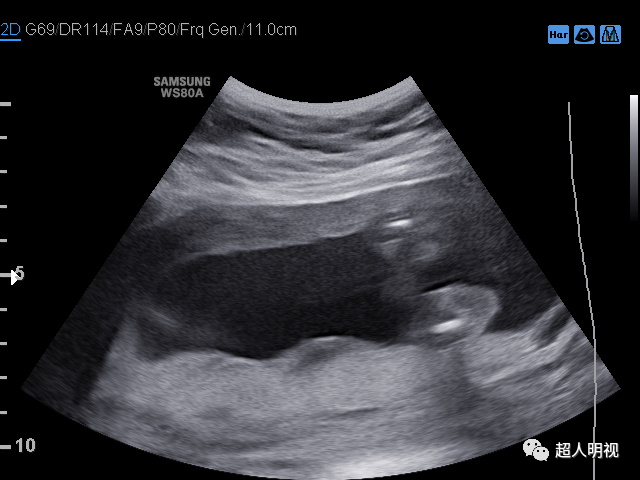

胎儿膀胱外翻的产前诊断

图片尺寸732x565

再谈容易漏诊的胎儿膀胱外翻

图片尺寸640x480